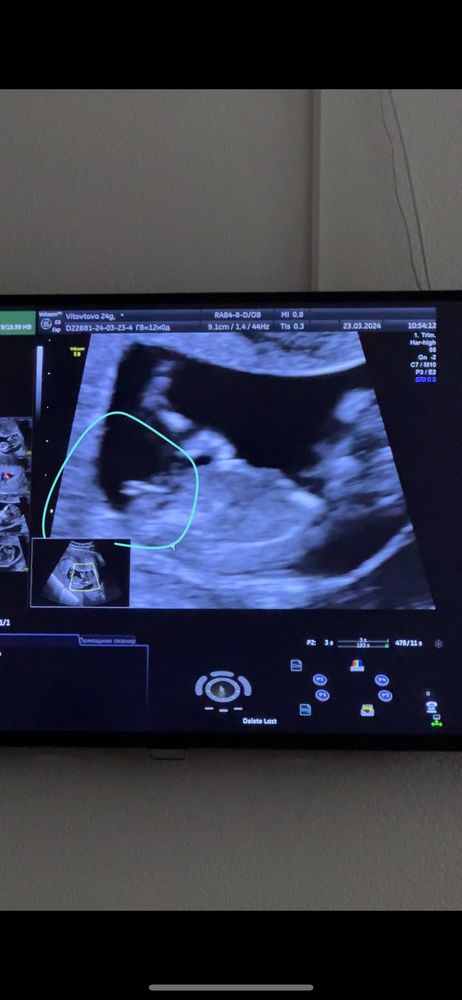

1 СКРИНИНГ ❤️ девчонка 80% носик мой☺️

Vale ria, уверенна на 99%, что девочка. Скоро узнаешь уже ))

Dina, на этом сроке еще ни "яек" ни "писюна" нет, есть только половой бугорок. Пол определяется по его наклону. Здесь явно девочка.